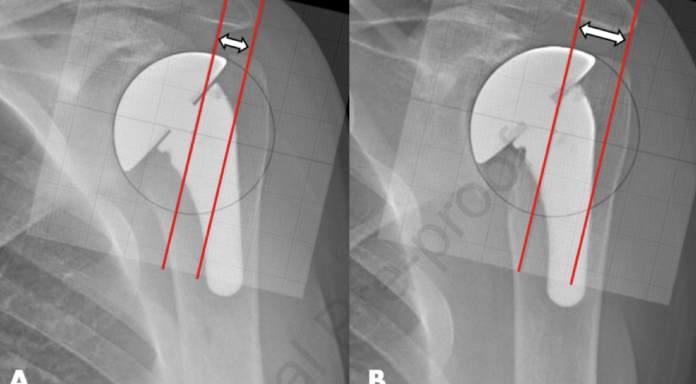

These measurements were compared between radiographs obtained immediately after surgery and at followup, the difference reflecting the amount of medialization: minimal/mild (≤5mm), moderate (between >5mm and ≤10mm) and substantial (>10mm).

Comparable radiographs of 113 shoulders with a mean radiographic follow-up of 6.7 years were analyzed. Minimal/mild glenoid wear was noted in 92 (81%) patients, moderate wear in 15 (13%), and severe wear in 6 (5%). The mean total glenoid wear was 2.9 ± 4.3 mm. Based on linear modeling, the glenoid wear rate was calculated at 0.3mm per year. The majority of glenoid wear occurred in the first four years after the ream and run arthroplasty and plateaued thereafter.

The authors of B2 and B3 glenoid osteoarthirtis: outcomes of corrective and concentric (C2) reaming of the glenoid combined with pyrocarbon hemiarthroplasty examined 41 shoulders with osteoarthritis and B2 and B3 glenoid pathoanatomy having corrective reaming of the glenoid and a pyrocarbon humeral hemiarthroplasty. The authors did not correlate clinical outcome with erosion rate. At an average follow up of 4.5 years , CT scan measurements showed that the average total medialization was 3.7 mm (2.0 mm due to reaming and 1.7 mm due to erosion). Note that the average rate of erosion was 1.7 mm / 4.5 years or 0.38 mm/year. This is the same rate of wear as noted in the study above using the chrome cobalt humeral head.